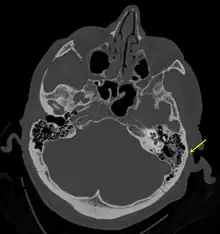

Temporal bone fractures

Acute injury to the internal carotid artery (carotid dissection, occlusion, pseudoaneurysm formation) may be asymptomatic or result in life-threatening bleeding. They are almost exclusively observed when the carotid canal is fractured, although only a minority of carotid canal fractures result in vascular injury. Involvement of the petrous segment of the carotid canal is associated with a relatively high incidence of carotid injury.[10]